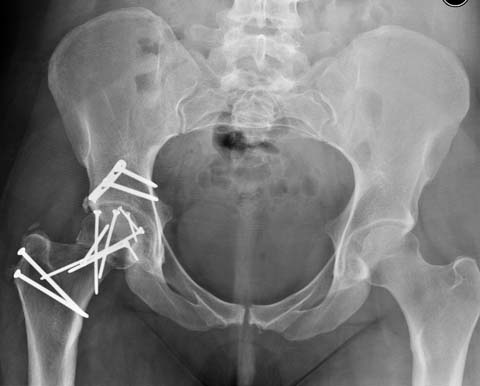

Здесь клинические примеры: Первый случай передний доступ, второй с ICP

monitor Flipp Trochanteris

и с переломом заднего края.